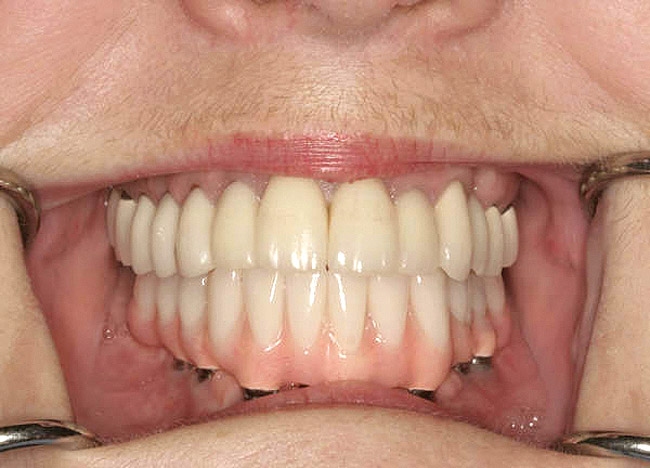

Figure 10c  Traditional fixed prosthodontics performed to level the opposing arch and regain sufficient crown height space.

Figure 10c

Figure 10d  Traditional fixed prosthodontics performed to level the opposing arch and regain sufficient crown height space.

Figure 10d

Diminished crown height space has several different solutions which depend on the patient’s anatomical limitations as well as his or her perceived needs. If the problem is the opposing arch, the solution may be fixed prosthodontics to level the occlusal plane (Figure 10A through Figure 10D). It may be intrusion of teeth with orthodontics or some combination of the two. If there is too little crown height space and the patient is edentulous, the solution may be to increase the vertical dimension of occlusion (VDO) with a removable prosthesis.17 If the patient has a partial dentition, it may involve traditional fixed prosthodontics to alter the VDO.18 The patient may need a surgical approach, such as an osteoplasty, before implant placement (Figure 11A and Figure 11B). However, without an initial diagnosis, there is no way of formulating a solution to an unknown problem.